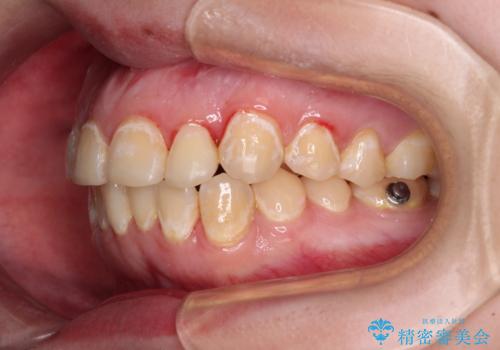

- 前歯のデコボコとクロスバイトが気になり、インビザラインによる矯正治療を希望して来院された患者様です。

上顎側切歯(上の真ん中から2番目の歯)が舌側転位している場合、無理して動かそうとすると歯髄壊死を起こすリスクが高い印象があります。

インビザライン単体でも治療は可能ですが、安全策としてインビザラインで歯列を移動する前に上顎前歯をワイヤー矯正で整え、その後上下歯列をインビザラインにて矯正治療を行うこととしました。

舌側転位している側切歯特有の、切縁の位置が不揃いであったり、根元が内側に引っ込んだ状態であったりという、インビザライン独特の仕上がりになることなく、きれいに整った歯列とすることができました。